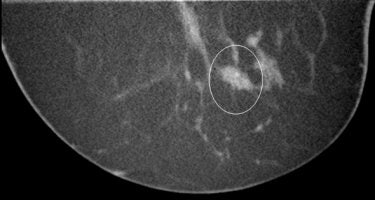

| A 4-mm intraductal carcinoma (IDC) on mammography (above) and breast CT (below). Image courtesy of John Boone, Ph.D. |